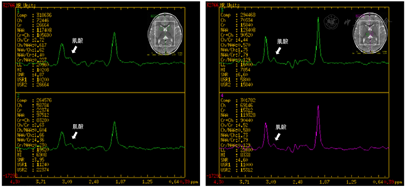

Gesell评估适应性相当于11.2月龄,发育商51,中度发育迟缓;大运动相当于11.2月龄,发育商51,中度发育迟缓;精细动作相当于10.0月龄,发育商46,中度发育迟缓;语言相当于7.9月龄,发育商36,重度发育迟缓;个人-社交相当于9.1月龄,发育商42,中度发育迟缓。脑电图示背景活动5~6Hz θ节律,未见明显异常放电。头颅MRI脑实质未见异常信号,局部脑外间隙略宽;MRS示双侧基底节区及丘脑肌酸峰降低(图1)。

患儿多次无热惊厥发作,Gesell评估示精神运动发育迟缓;头颅MRI脑实质未见异常信号,局部脑外间隙略宽;MRS示双侧基底节区及丘脑肌酸峰降低;高通量测序发现患儿X染色体SLC6A8基因剪接变异。结合患儿精神运动发育迟缓,癫痫发作,头颅MRS改变,故患儿诊断为SLC6A8基因变异导致的脑肌酸缺乏综合征1型。

由于患儿肌酸不能通过肌酸转运蛋白进而代谢为肌酐,因此患儿血及尿肌酐降低,尿肌酸与肌酐比值增高,此为一种可靠的筛查方法;杂合子女性该比值可在正常范围或轻度升高;本例患儿多次检测血肌酐正常低界。关于影像学检查,头颅MRI往往无明显异常或显示轻度异常。van de Kamp等[7]对肌酸转运蛋白缺陷症表型进行回顾性分析,76例进行头颅MRI检查者中53例存在轻度异常,包括轻度髓鞘形成延迟、胼胝体薄、轻度脑室或脑外间隙增宽及脑萎缩;66例进行头颅MRI检查者均显示肌酸完全缺失或严重降低。头颅MRS肌酸峰降低与基因检测有助于进一步确诊。Duran-Trio等通过敲入Slc6a8基因点突变建立CTD大鼠模型,发现这些雄性大鼠脑肌酸降低,尿肌酸/肌酐比值升高,并出现认知障碍和自闭症样行为[14]。因此,大鼠模型研究亦证实了SLC6A8基因突变者的临床表型。